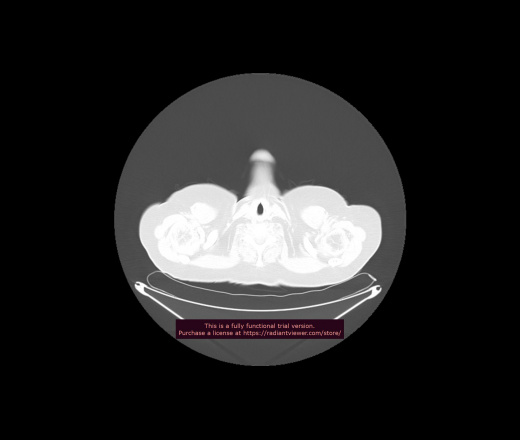

Уважаемые коллеги, если имеется интерес, сможете ли Вы спрогнозировать дальнейшее +-одинаковое течение процесса у 4 данных разных пациентов? Зацепиться где-то можно очень просто, где-то нельзя.